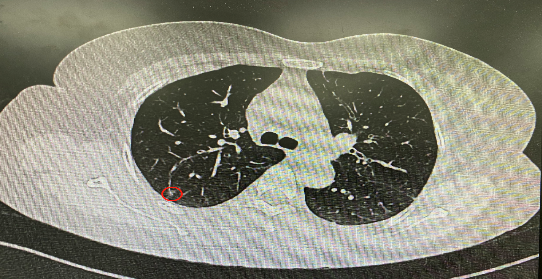

今年54歲的李女士(化名)7月初突然出現(xiàn)右上部腹痛,起初并未在意,以為稍作休息就會好轉(zhuǎn),但疼痛卻并未消退,持續(xù)了一個星期。李女士實在難以忍受,才在家人陪伴下來到西安國際醫(yī)學(xué)中心醫(yī)院就診。胸外科二病區(qū)崔凱主任接診患者后,詳細(xì)詢問病情并查閱檢查資料,經(jīng)胸部HRCT檢查,結(jié)果提示:右肺上葉后段混合密度結(jié)節(jié)影,考慮原位癌可能,即將患者收入胸腔外科二病區(qū)住院治療。

經(jīng)與患者家屬溝通,崔凱主任決定行外科手術(shù)治療。為達到精準(zhǔn)切除,術(shù)前需進行肺小結(jié)節(jié)切除前定位。由于結(jié)節(jié)位于右肺上葉后段,傳統(tǒng)經(jīng)胸外穿刺術(shù)無法抵達病灶。崔凱主任與呼吸內(nèi)科一病區(qū)歐陽海峰主任討論后,決定擬行LungPro全肺診療導(dǎo)航下染色定位。即術(shù)前通過Lung Pro導(dǎo)航規(guī)劃染色位置,經(jīng)Lung Pro實時引導(dǎo)支氣管鏡抵達既定位置,注入亞甲藍染色劑標(biāo)記結(jié)節(jié)位置。

使用術(shù)前規(guī)劃系統(tǒng)重建全肺3D模型,并于外科醫(yī)生討論染色位置,最終確定標(biāo)記染色點—右肺上葉后段b亞段(RB2b)。術(shù)中使用P290(4.9mm外徑)標(biāo)準(zhǔn)支氣管鏡,根據(jù)導(dǎo)航術(shù)前規(guī)劃路徑,Lung Pro實時導(dǎo)航下,GS鞘管進入RB2b遠端官腔外病灶并注射亞甲藍染色劑。

一切準(zhǔn)備就緒,7月15日,崔凱主任團隊聯(lián)合歐陽海峰主任團隊為患者行單孔胸腔鏡下右肺上葉后段切除術(shù),手術(shù)用時128分鐘順利完成。進入胸腔后,亞甲藍染色部位明顯,患者發(fā)生癌變的右肺上葉后段被成功切除。術(shù)后標(biāo)本根據(jù)染色部位迅速找到結(jié)節(jié),剖開位置兼染色位置和病灶完全符合,行術(shù)中冰凍后快速送病理檢查。經(jīng)術(shù)后病理檢查,明確診斷為(右肺上葉)原位腺癌。